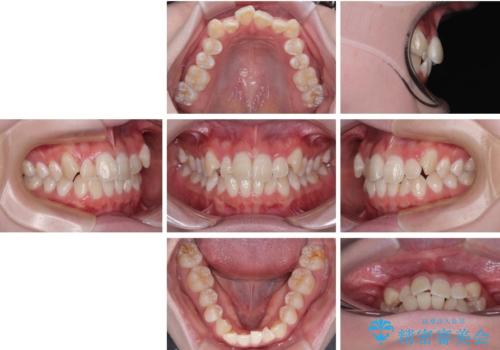

- 「前歯のデコボコ(叢生)をきれいに整えたい」とのことでご来院されました。

患者様の協力もあり、およそ1年間で治療を完了。スムーズな歯の移動を実現しました。

上下の正中(真ん中のライン)もずれることなく、バランスの取れた美しい歯並びに。笑顔に自信を持てる仕上がりとなりました。

「もっと時間がかかると思っていましたが、あっという間でした。装置も思ったより気にならず、前歯がきれいに並んでとても満足しています。」とうれしいお言葉をいただきました。